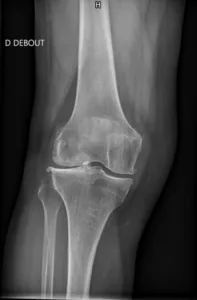

Radiographies standard :

- Les radiographies en charge sont l’examen de base pour diagnostiquer la gonarthrose.

- Elles mettent en évidence un pincement de l’interligne articulaire, des ostéophytes (excroissances osseuses), une sclérose de l’os sous-chondral et parfois des géodes (petites cavités osseuses remplies de liquide).